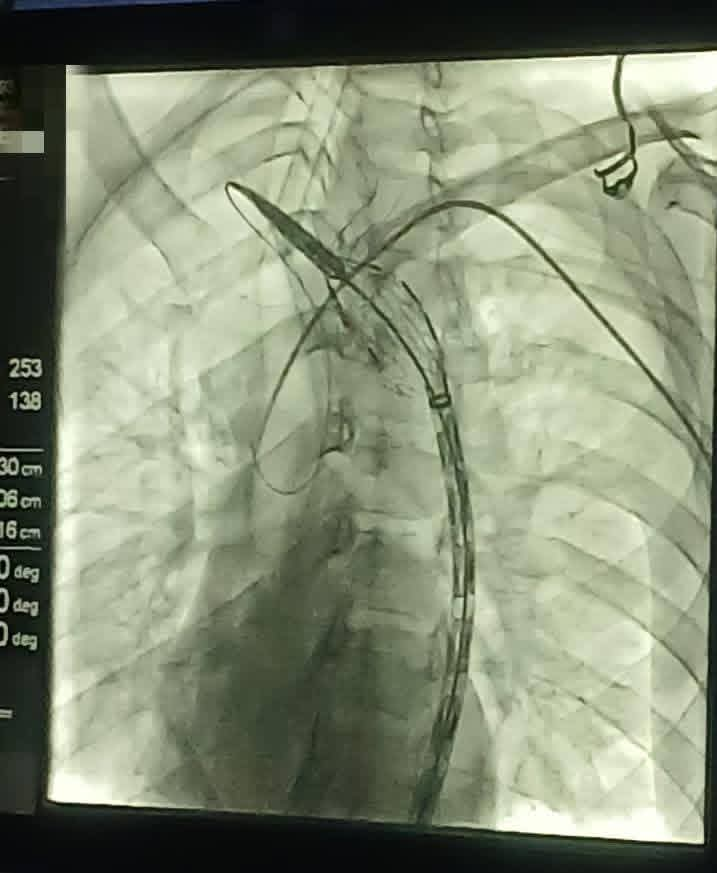

استقبل المستشفى الجهوي بجربة، يوم 8 أفريل 2026، شابًا يبلغ من العمر 24 سنة، أصيل معتمدية بني خداش، وذلك إثر تعرّضه لحادث مرور خلّف له إصابة بليغة تمثّلت في تمزّق على مستوى الشريان الأبهر (lésion traumatique de l’isthme de l’aorte)، وهي حالة تستوجب تدخّلًا طبيًا عاجلًا نظرًا لخطورتها. وبحسب المعطيات المتوفرة، تمّ اتخاذ قرار سريع بتوفير فريق طبي مختصّ في جراحة القلب والشرايين، حيث جرى نقل فريق يقوده الدكتور جلال الزيادي من مستشفى الرابطة بالعاصمة إلى جزيرة جربة على متن مروحية تابعة للحرس الوطني. وقد تمّ التدخل الجراحي داخل قاعة القسطرة بإحدى المصحات الخاصة بالجهة، وذلك في إطار تنسيق بين القطاعين العمومي والخاص. وأفادت المصادر ذاتها بأن العملية تكللت بالنجاح، وأن الحالة الصحية للمصاب وُصفت بالمستقرة في الوقت الحالي. ويأتي هذا التدخل في سياق الجهود المبذولة لضمان التكفل بالحالات الصحية الاستعجالية، خاصة تلك التي تتطلب خبرات وتجهيزات دقيقة غير متوفرة في بعض الجهات.